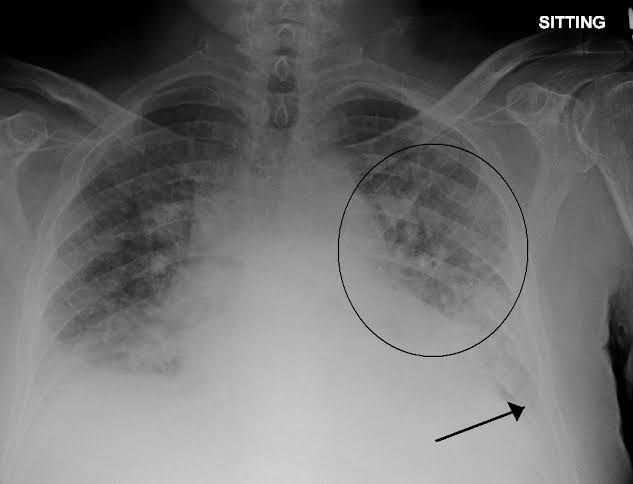

Pulmonary edema is a condition caused by too much fluid in the lungs. This fluid collects in the many air sacs in the lungs, making it difficult to breathe. In most cases, heart problems cause pulmonary edema. But fluid can collect in the lungs for other reasons. These include pneumonia, contact with certain toxins, medications, trauma to the chest wall, and traveling to or exercising at high elevations.